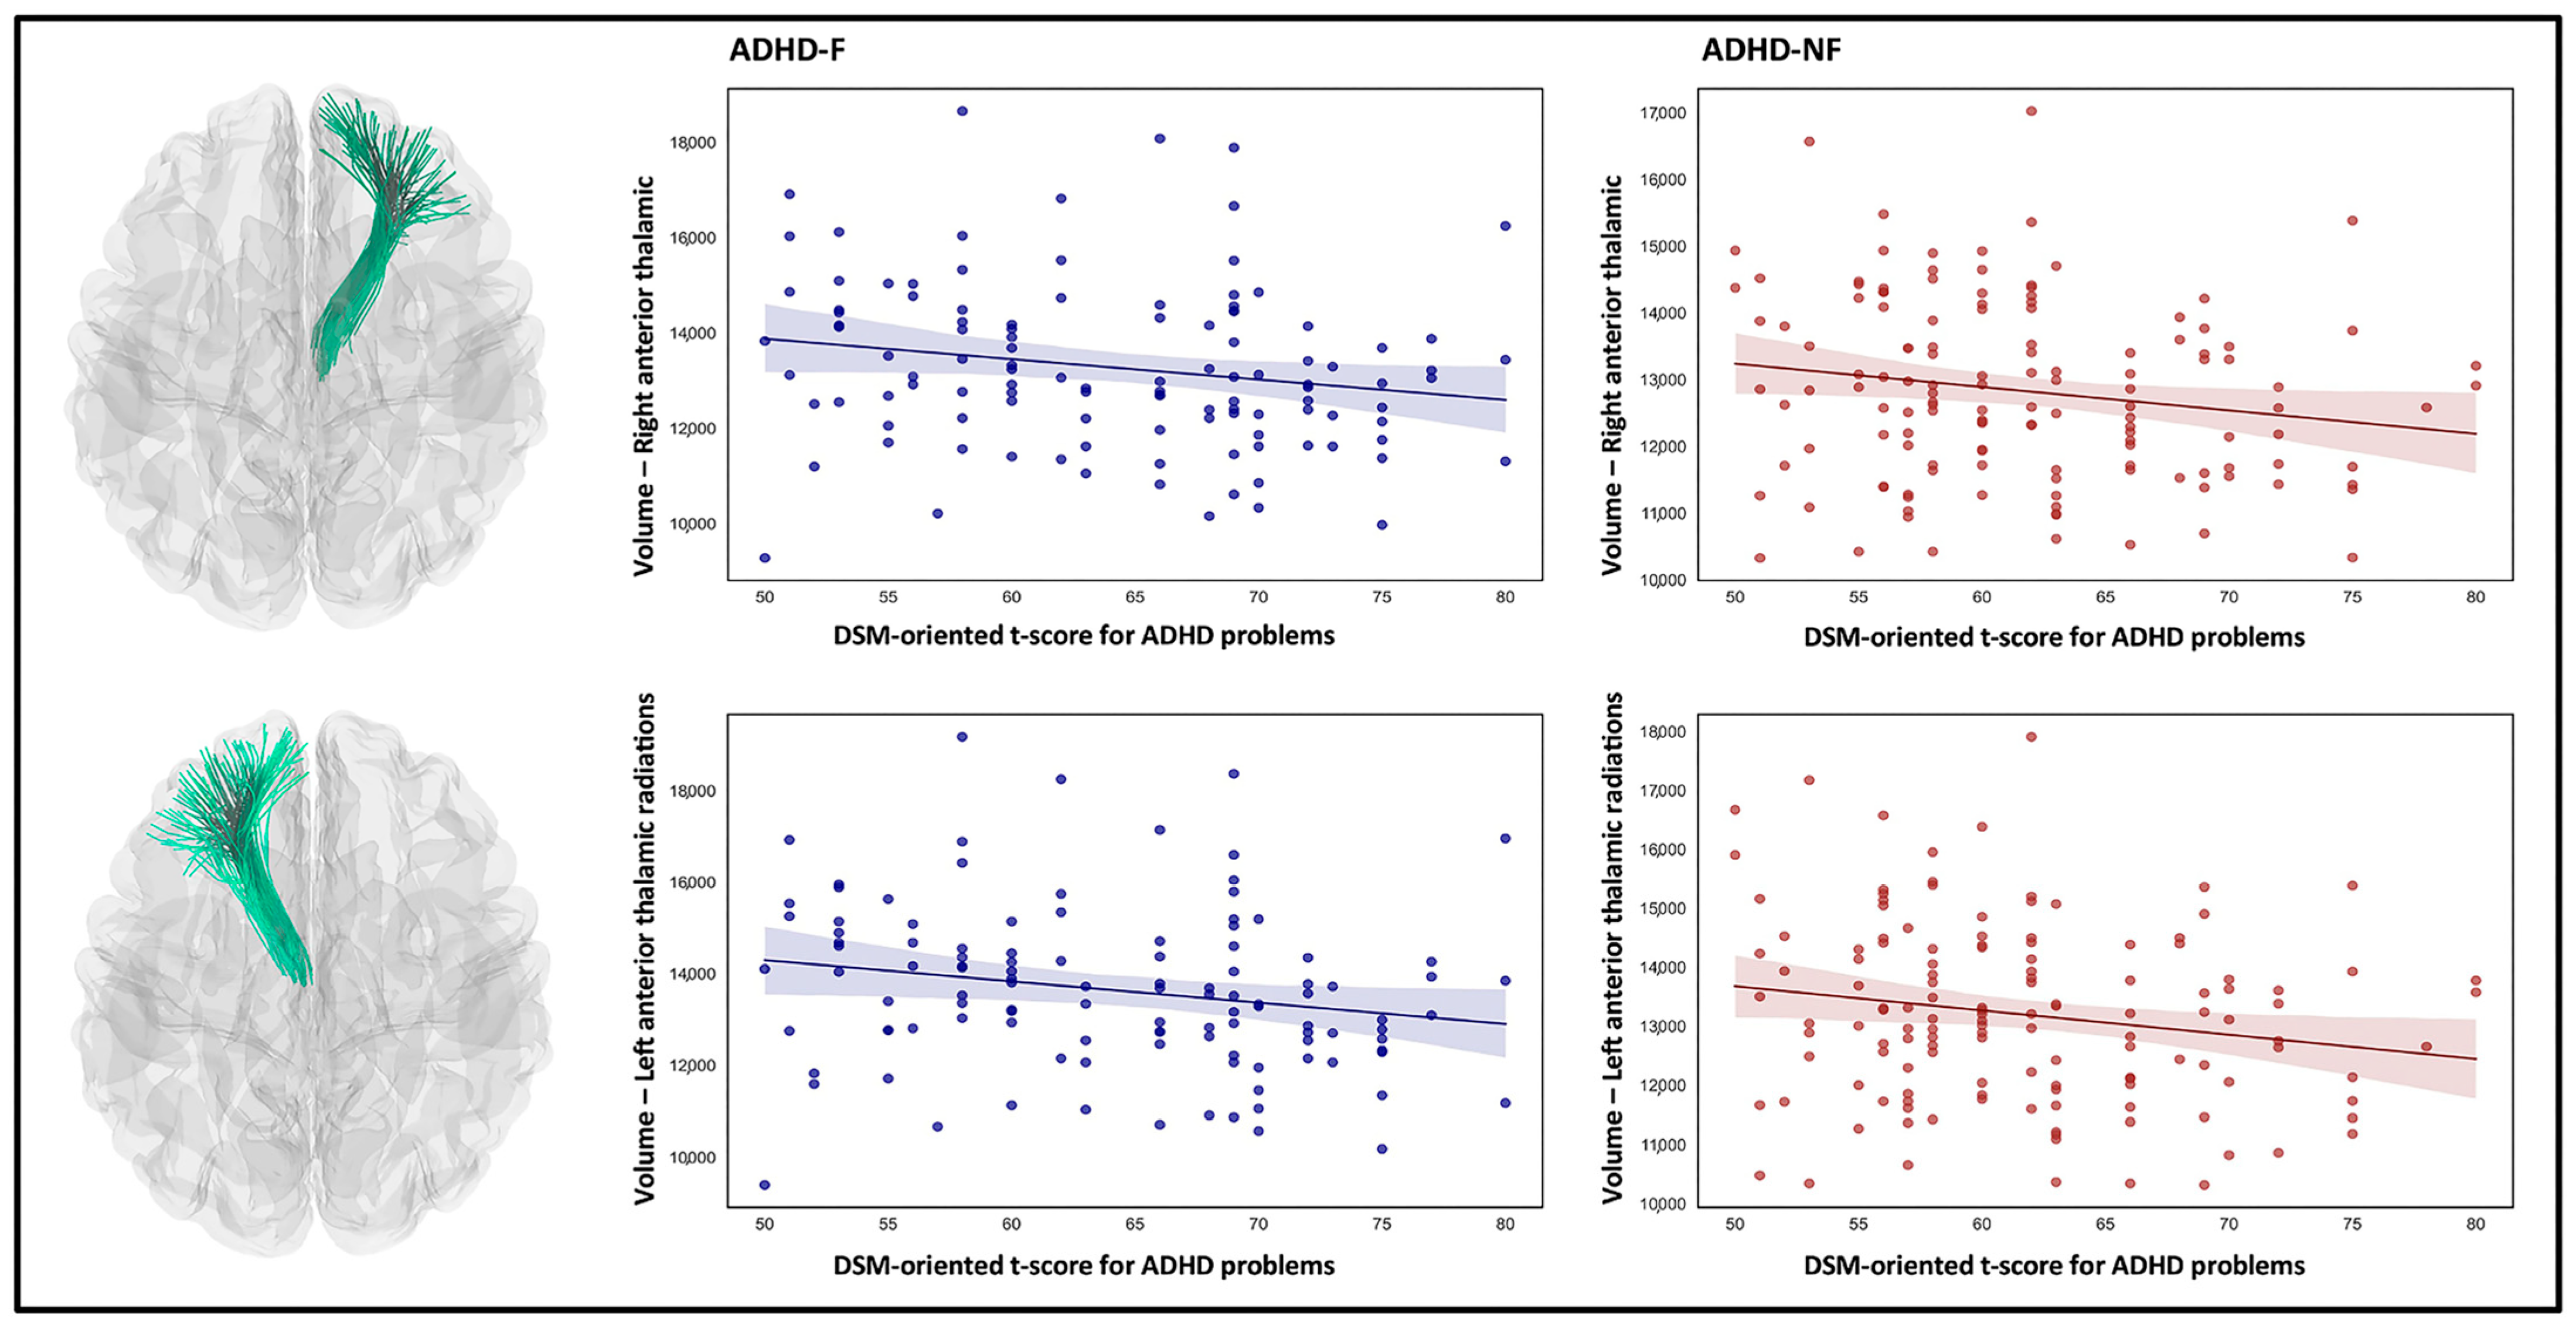

3. Results